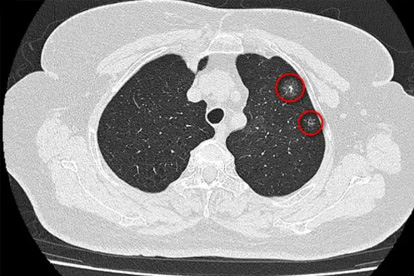

肺癌作为高发恶性肿瘤,早期诊断和规范治疗对提高生存率至关重要。广州作为华南医疗中心,汇聚了多家在肺癌诊疗领域具有丰富经验的三甲医院,为患者提供多学科协作的综合治疗方案。

肺癌预防需要从日常生活做起。戒烟是重要的预防措施,同时要避免二手烟暴露。注意室内通风,减少厨房油烟接触。定期进行低剂量CT筛查对高危人群尤为重要。保持健康饮食,多摄入新鲜蔬果,适量运动,增强免疫力。出现持续咳嗽、胸痛、咯血等症状应及时就医检查。确诊肺癌后要积极配合医生治疗,保持乐观心态,有助于提高治果和生活质量。